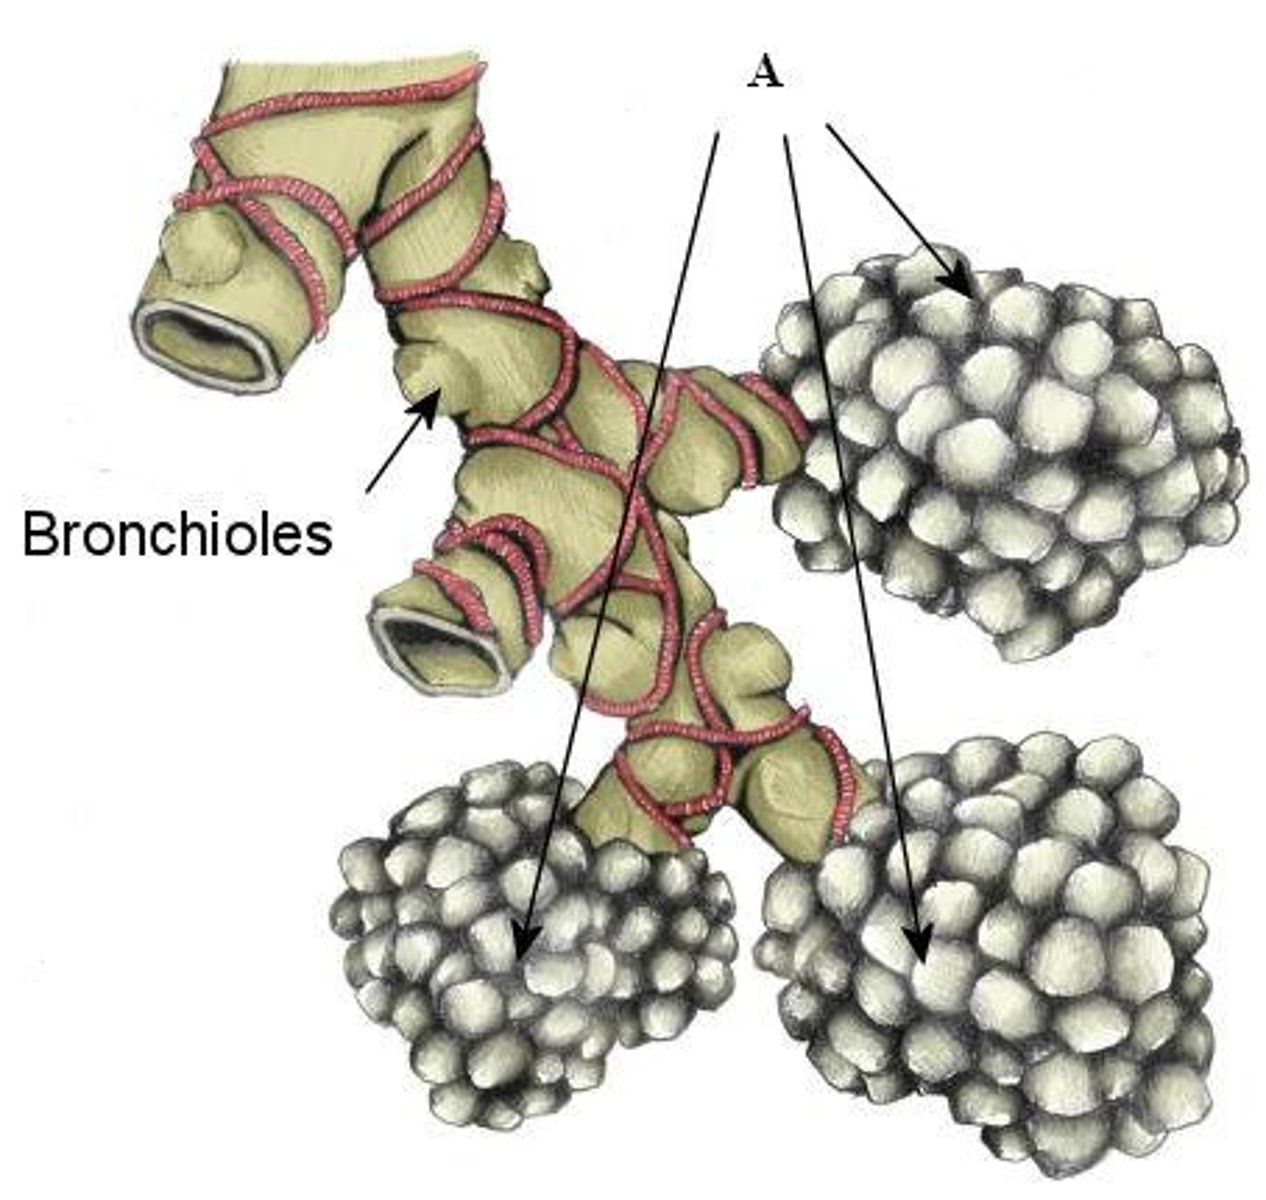

bronchial tree

collective name for the multiple branches of the bronchi and bronchioles of the respiratory system

bronchiole

branch of bronchi that are 1 mm or less in diameter and terminate at alveolar sacs

respiratory bronchiole

branches of the terminal bronchioles that subdivide into several alveolar ducts

alveous

small, grape-like sac that performs gas exchange in the lungs